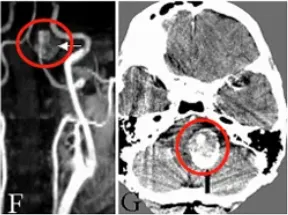

病人在手术当天即神志清楚,没有出现新发的神经功能缺损。在术后第一天的检查中,未发现局部或远端梗死和吻合口再出血(图2A-B)。MR显示脑干压迫效应解除(图2C-和D),术后血管造影显示吻合的PICA充盈良好、血流通畅(图2E-F)。术后恢复顺利,无术后并发症。经过7年的随访,声带麻痹已痊愈,生活正常。

图2A-B:CT显示动脉瘤囊切除和VA-PICA吻合术后,远外侧入路的骨磨除部分。

图2C-D:术后MR显示动脉瘤体切除。

图2E-F:术后血管造影显示成功的VA-PICA吻合术,不同直径的VA(星号)和PICA(双箭头)以及远端VA上的永久夹闭(单箭头)。